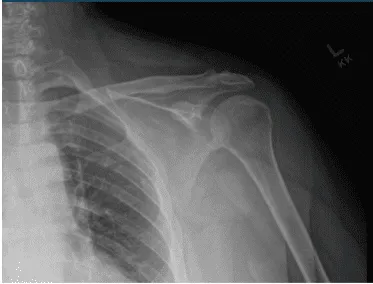

Se presentaron y discutieron radiografías del hombro izquierdo y mostraron radiografías normales del hombro izquierdo. Recomendó al paciente que se sometiera a una resonancia magnética para ver la causa del dolor. Descubrí que hay muy poca osteoartritis articular AC. No se visualiza ningún entesófito subacromial. También se notó una leve tendinosis del manguito rotador.

Radiografía del hombro izquierdo